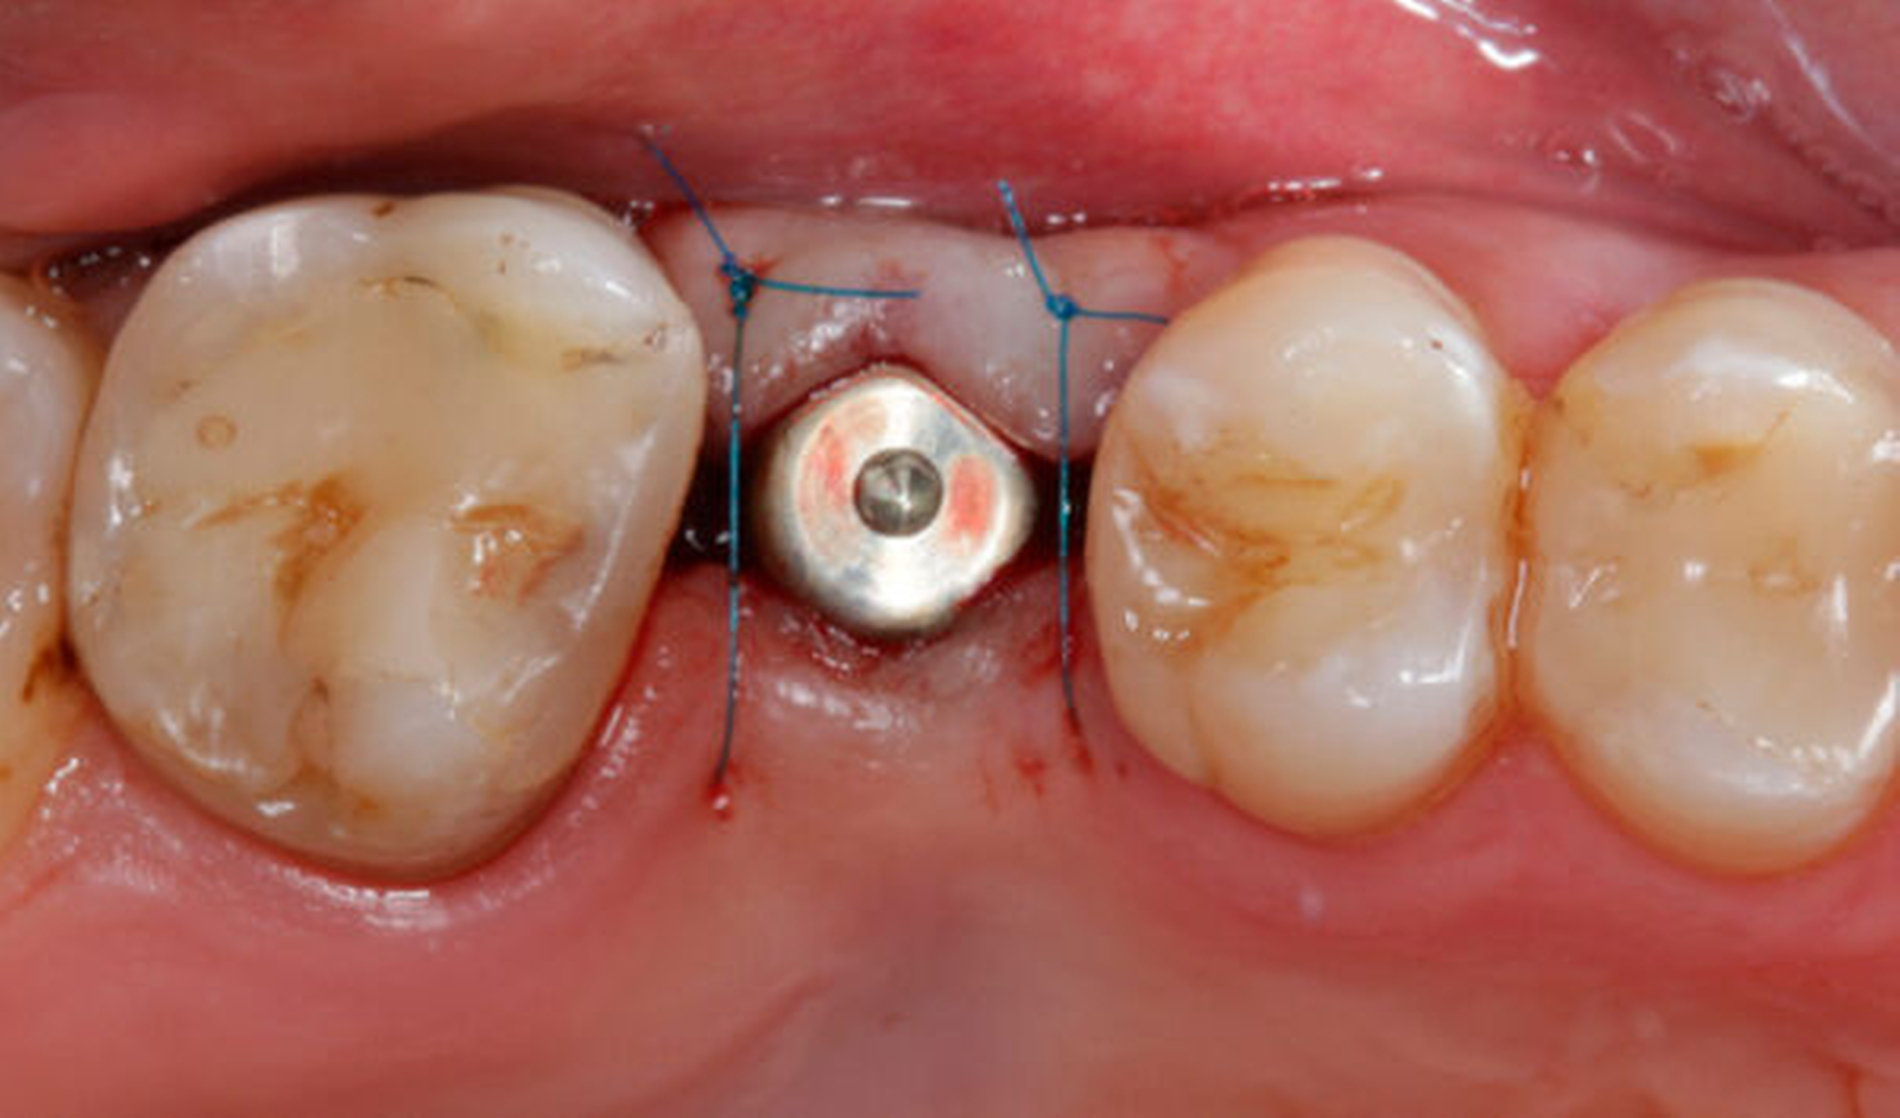

Mit den in den letzten Jahren ausgeweiteten Indikationen ist auch die Notwendigkeit verbunden, mehr Risikofaktoren zu kontrollieren. Der Beitrag erörtert verschiedene Indikationen und gibt einen praxisnahen Einblick in die implantologische Lückenversorgung.

Autoren: Mats W. H. Böse, Jeremias Hey, Maria Bruhnke, Florian Beuer (Berlin)

Die bislang selten angewandte Zahnextrusion bietet die Chance, selbst Zähne mit tiefen Defekten erfolgreich zu behandeln. Die kieferorthopädische Extrusion hat zudem den Vorteil, dass im Fall des Zahnverlusts eine „augmentierte“ Einzelzahnlücke verbleibt, die eine weitere implantologische Versorgung erleichtern kann.